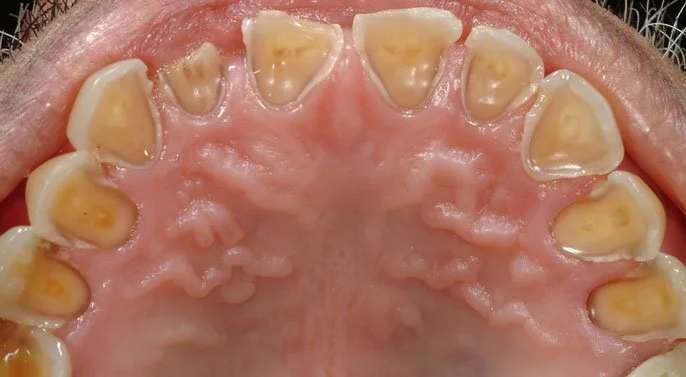

Cavities (Tooth Decay): Cavities are caused by bacteria that eat away at your tooth enamel. Early stages might just feel like mild sensitivity, but untreated decay can reach the inner layers of the tooth, causing severe pain and even infections.

Gum Disease: Gingivitis or periodontitis can lead to inflamed, bleeding gums and discomfort while eating. Advanced gum disease can even cause tooth loss if left untreated.